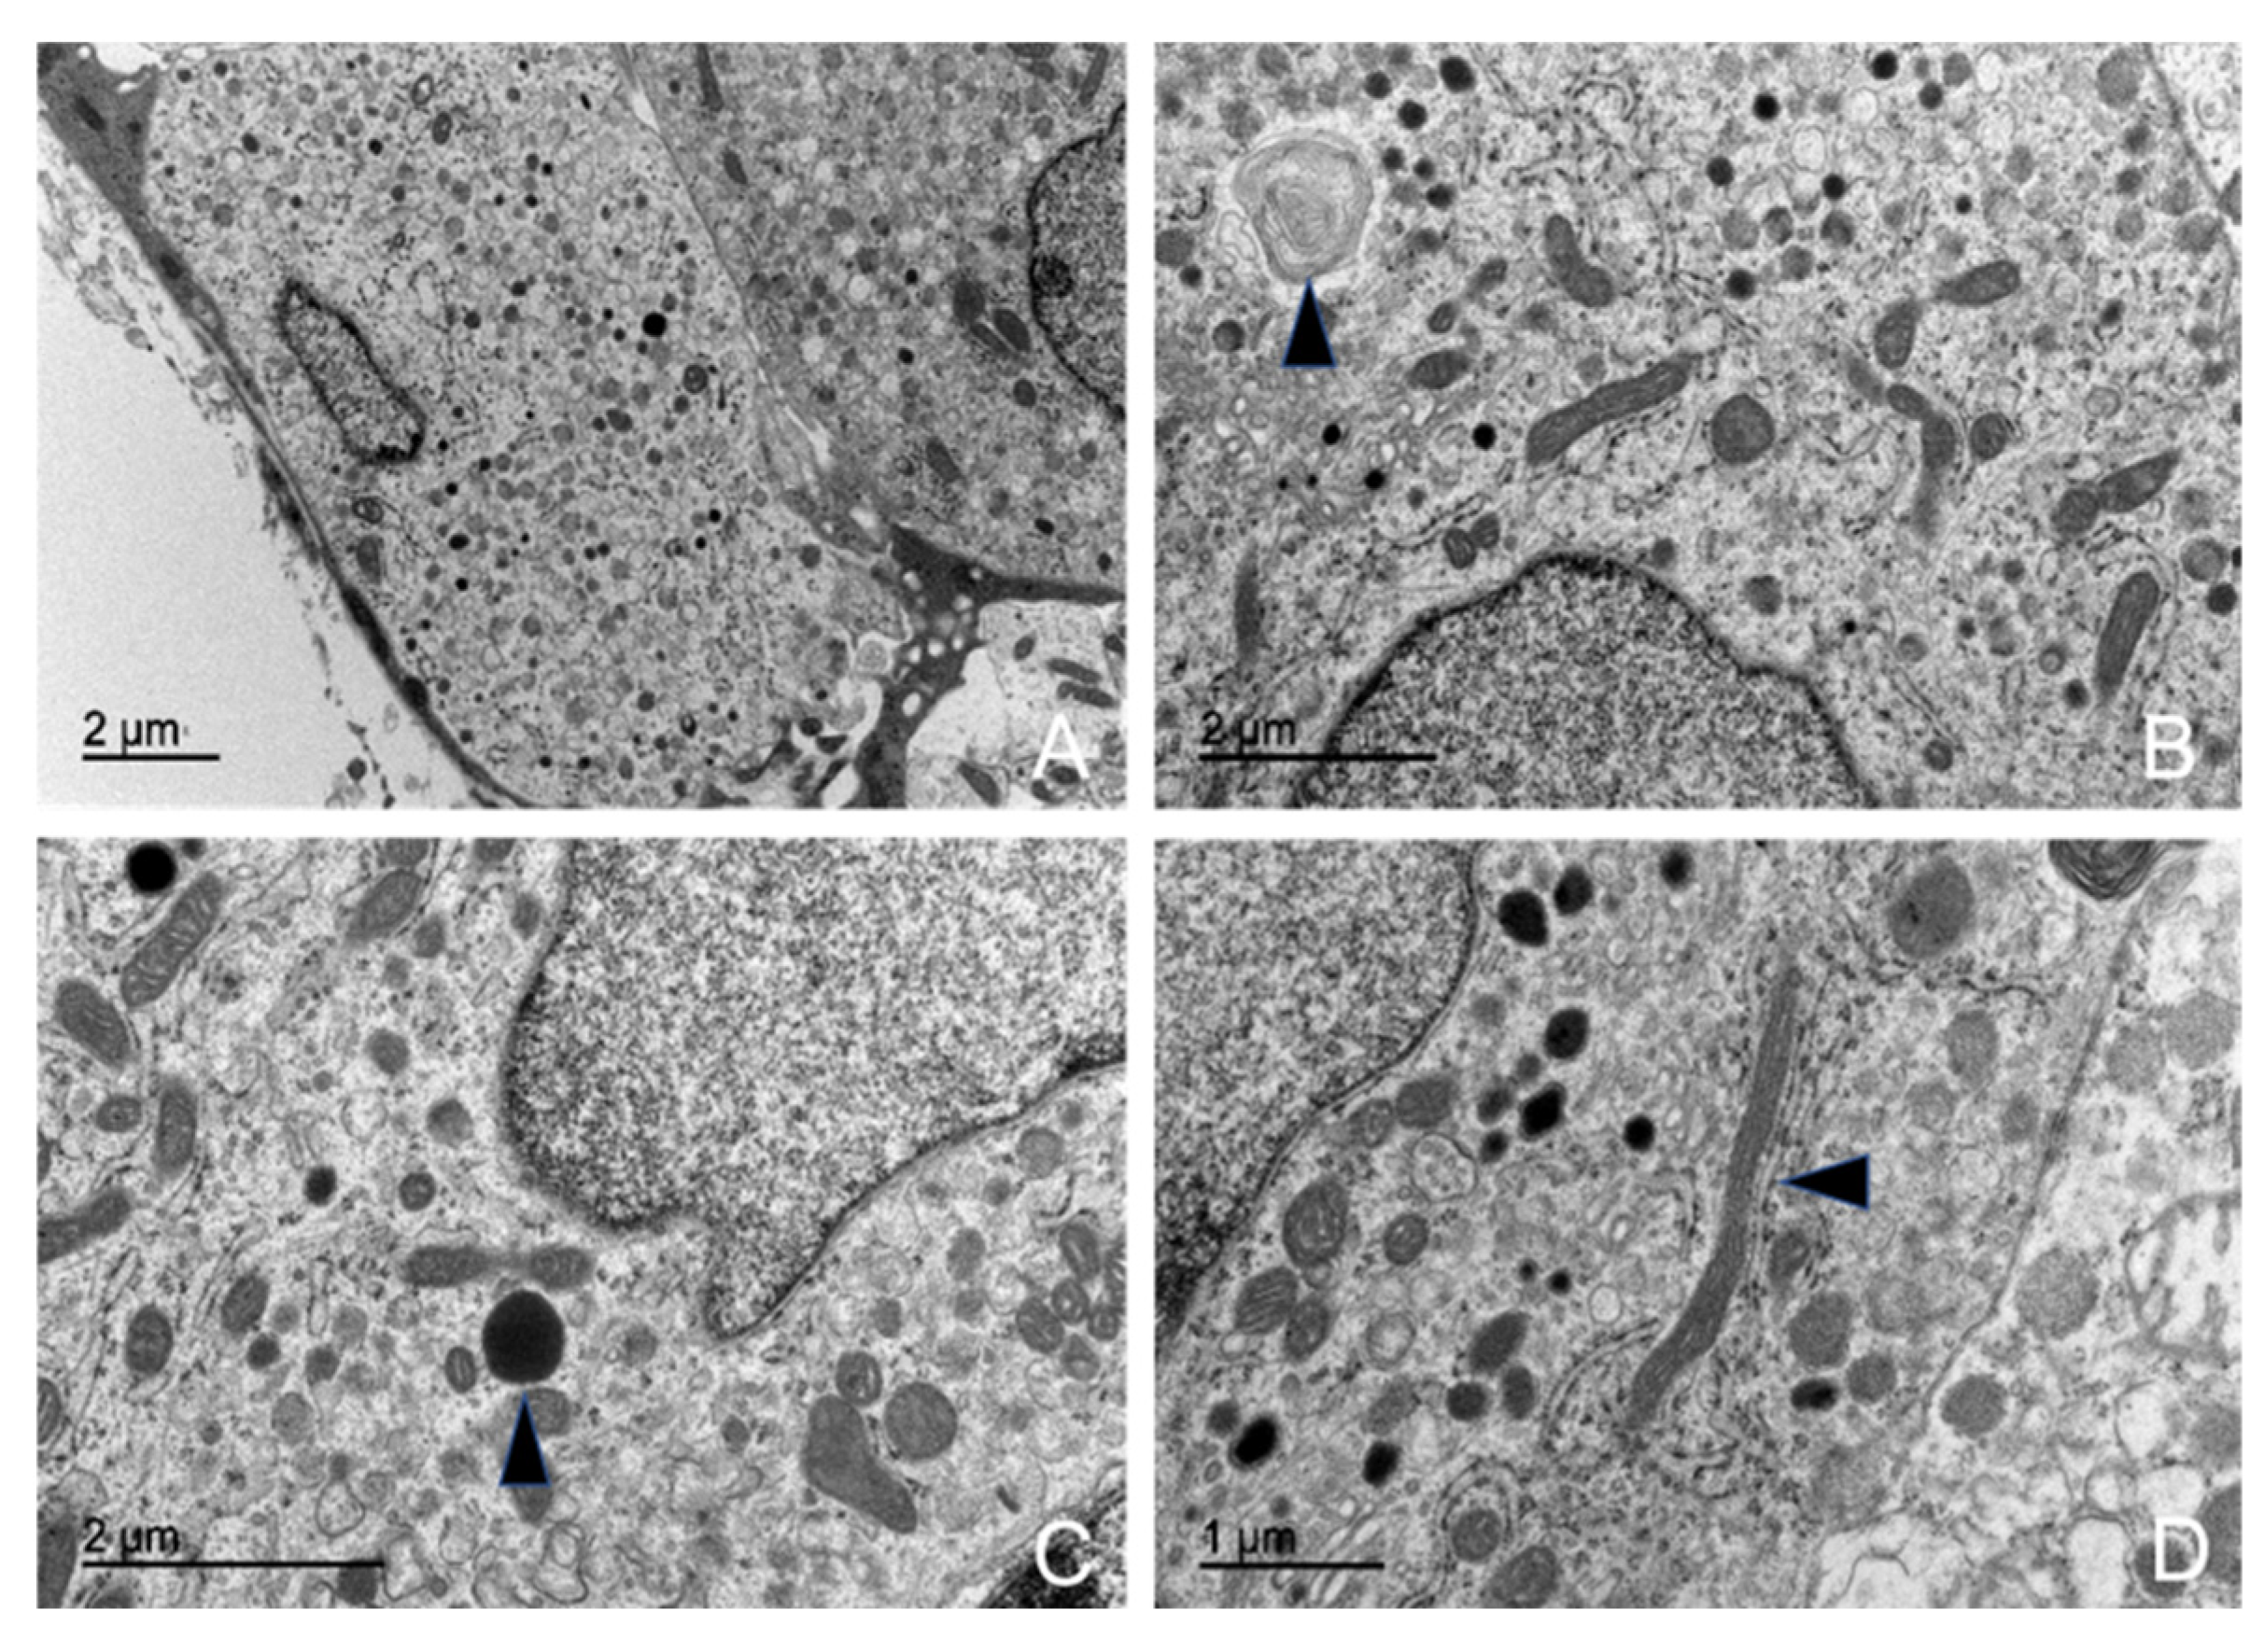

3.5. Ultrastructural Description of the Adenohypophysis Through Transmission Electron Microscopy (TEM)

3.5.1. Corticotrophs (ACTH-Producing Cells)

3.5.2. Lactotrophs (LTH-Producing Cells)

3.5.3. Somatotrophs (GH-Producing Cells)

4.3. Ultrastructural Study